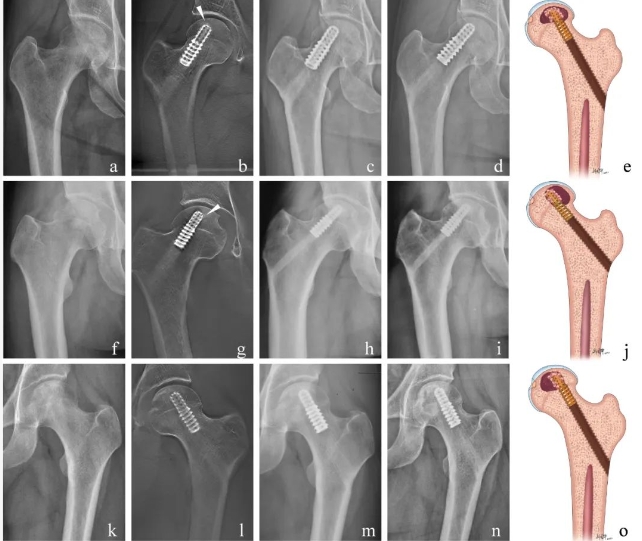

论文中展示的成功案例,并通过影像学随访结果总结成功模式

该研究主要结果是证实了AVN CAGE的早期保关节疗效,对2018年8月至2021年12月于我院进行AVN CAGE植入的59例髋关节进行随访,患者平均年龄39.5岁,且均处于股骨头坏死早中期。在术后平均22.2个月时,47例髋关节在影像学上没有进一步进展至髋关节塌陷,而53例髋关节没有接受人工全髋关节置换;临床评分结果则显示术后髋关节症状和功能均得到明显改善,而术后复查影像学则显示假体与周围骨形成了良好的骨整合。生存数据显示在术后2年时AVN CAGE的临床保关节成功率达到88.9%,与既往报道的传统人工骨(平均30个月时临床成功率75.9%)和钽棒植入(平均29个月时临床成功率75.4%)等方式相比取得了疗效上的进步,对延缓骨坏死疾病进展是安全有效的。